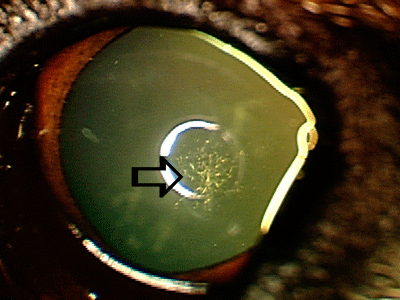

Cataract surgery is effective method for permanently removing cataracts and restoring normal vision. Artificial lens (white arrow) is usually placed in the eye with a goal of correcting vision to the normal levels. Removal of cataracts eliminates risks of chronic cataract-induced inflammation, and associated complications, which may result in blindness and loss of eye (retinal detachment, glaucoma, intraocular hemorrhage).

Cataract surgery is effective method for permanently removing cataracts and restoring normal vision. Artificial lens (white arrow) is usually placed in the eye with a goal of correcting vision to the normal levels. Removal of cataracts eliminates risks of chronic cataract-induced inflammation, and associated complications, which may result in blindness and loss of eye (retinal detachment, glaucoma, intraocular hemorrhage).